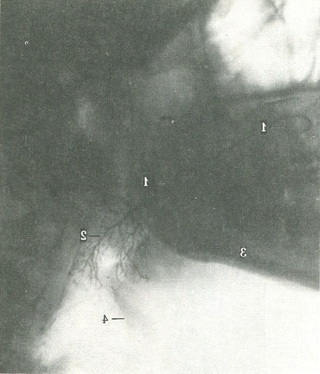

Після введення контрастної речовини в протоку будь слинної залози (сиалография) по контуру і архітектурі проток можна судити про стан залози. Контури протоки чіткі, мають рівномірний діаметр, архітектура дольковых проток правильна, порожнечі відсутні; як правило, легко заповнюються протоки 5-го, 4-го, 3-го, 2-го і 1-го порядку, які мають деревоподібну форму (рис. 225). Всі протоки звільняються від контрастної речовини протягом першої години після введення.

225. Бічна сиалограмма лівої привушної слинної залози.

1 - протока; 2 - внутрижелезистые слинні протоки; 3 - нижня щелепа; 4 - під'язикова кістка.